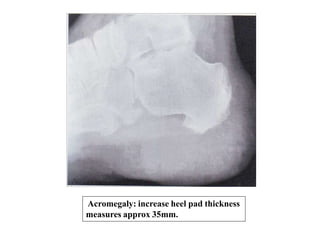

Feet show increased thickness of heel pad

Acromegaly: increase heel pad thickness

measures approx 35mm.